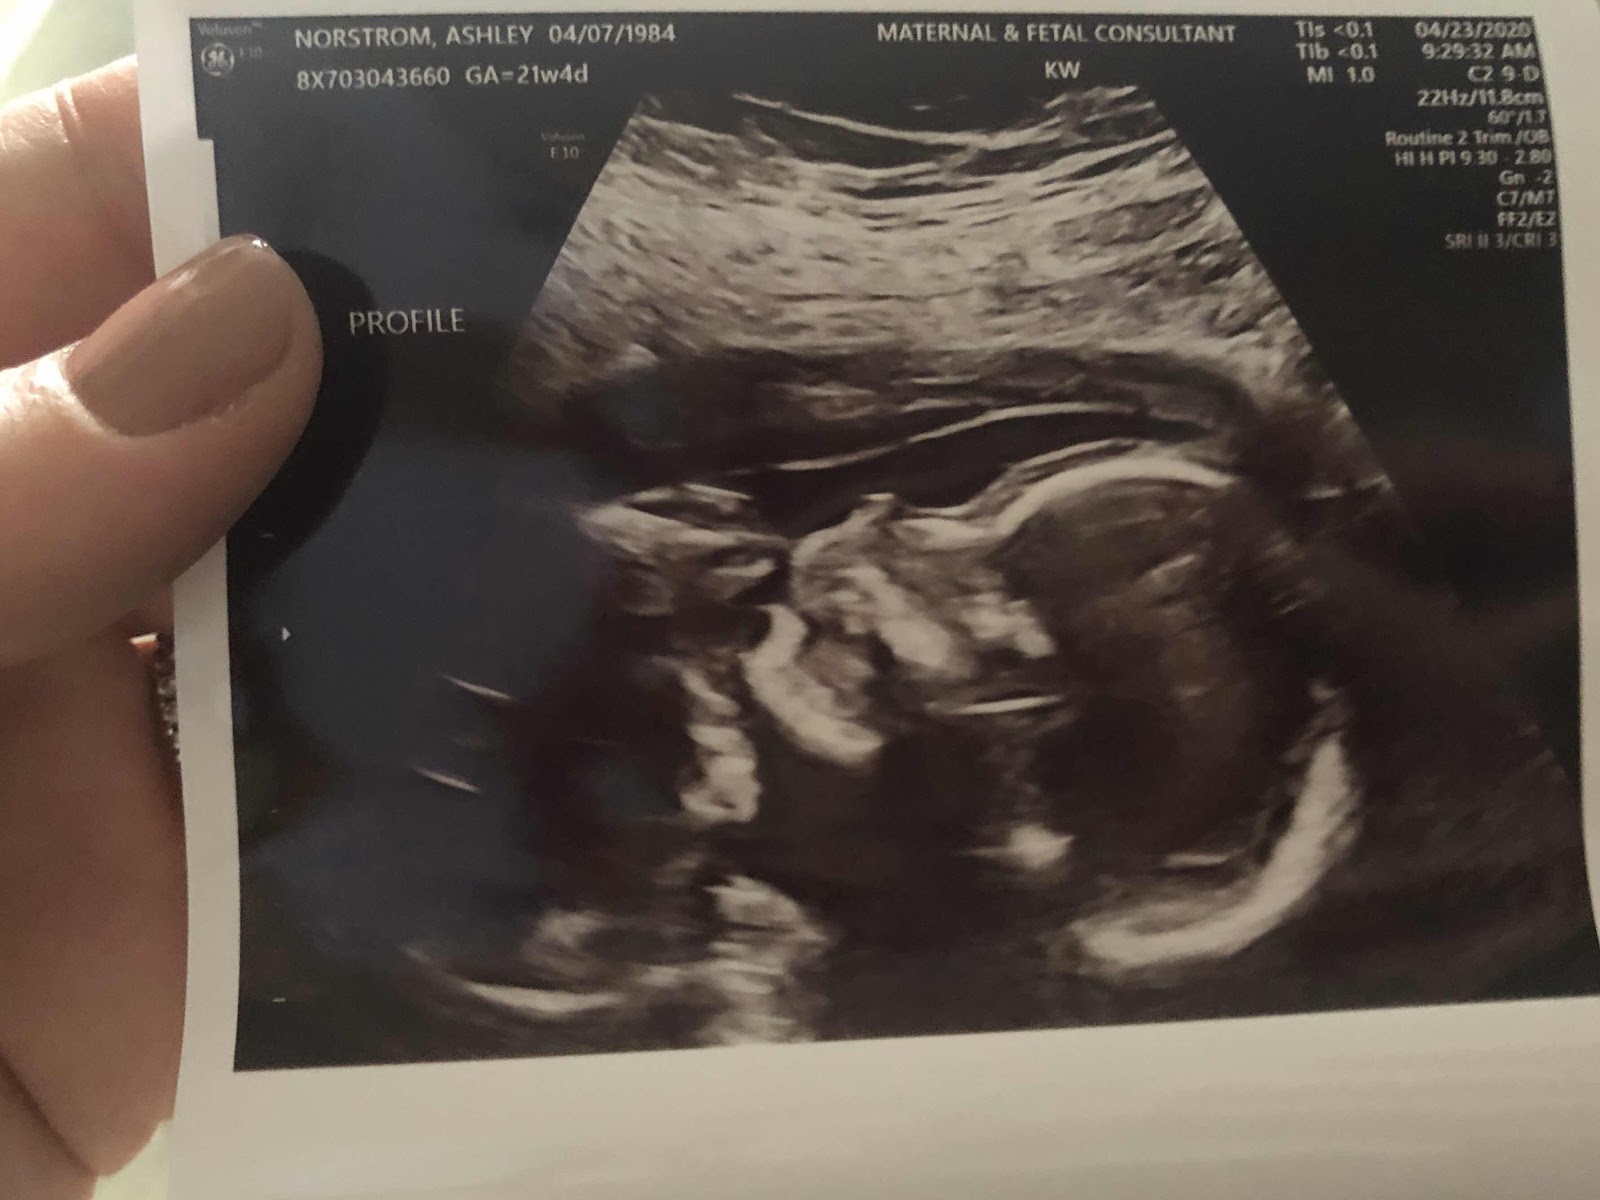

I had my follow-up ultrasound with MFM a few days ago on Thursday.

My fluid level went up from a 7 to a 10 and the largest placental lake decreased in size from 5cm to 3cm. I couldn't have asked for better news! The doctor stated I could decrease my water intake from 120oz per day to 80oz, which is much more manageable. I don't go back to see her for another month. Fingers crossed. There was no more scary talk about worst case scenarios and early deliveries. WHEW